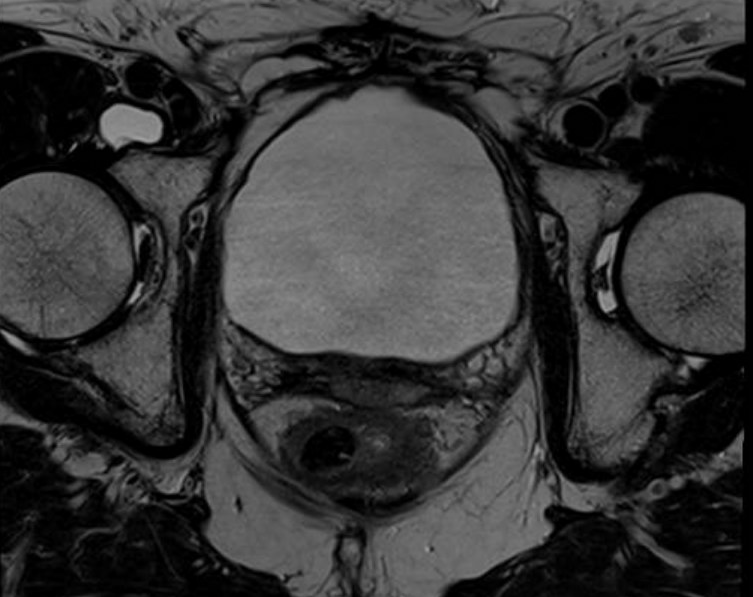

Figure 1 and figure 2 illustrate the typical interfraction movement as seen on the MRI scan. Figure 3 and figure 4 demonstrate the daily changes of the patient’s internal anatomy whilst figure 5 and figure 6 show the adaptive radiotherapy plan.

Fig 5: Radiotherapy plan

Fig 6: Plan adaptation. Tight conformality at rectal and prostate boundary is demonstrated by the arrow. Rapid reduction of high dose optimises dose delivery to the prostate and limit dose to the rectum, reducing the risk of long term toxicity.